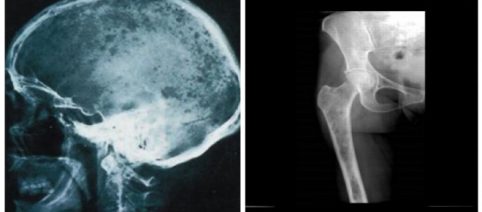

Niños

Cirujanos de Israel vuelven a colocar la cabeza a un niño con ‘decapitación interna’

Tras ser arrollado el niño de 12 años quedó con su cráneo separado de las vértebras superiores de la columna

Tras ser arrollado el niño de 12 años quedó con su cráneo separado de las vértebras superiores de la columna -